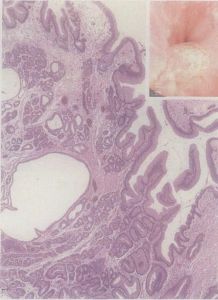

增生性息肉,又稱 化生性息肉,多發生在直腸,多數40歲以後發病,隨年齡增長,發病率增高。息肉的數目雖多,但無明顯的症狀,偶有大便帶鮮血。鏡下可見息肉體積小、均等、表面光滑、蒂短。本病無癌變傾向。目前該病的病因尚不清楚。一般不需特殊治療。

MVSP的隱窩上部有大量富含微泡的柱狀細胞,鋸齒狀結構顯著。在某些位於近側結腸的病變中,這種鋸齒狀結構甚至沿隱窩向下延伸。

GCSP的隱窩上部和表面被復許多成熟杯狀細胞,鋸齒狀結構不如前者顯著。以後的分子生物學研究結果有力地支持該分類方法。